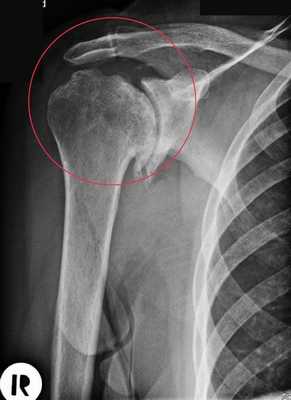

- остеонекроз - отмирание клеток головки кости;

- многооскольчатые сложные переломы и раскол головки;

- плохо сросшиеся старые переломы без возможности восстановления нормальной анатомии сустава;

- артрит;

- необратимые патологии вращательной манжеты;

- опухолевые заболевания.

Артроз плечевого сустава на рентгене.